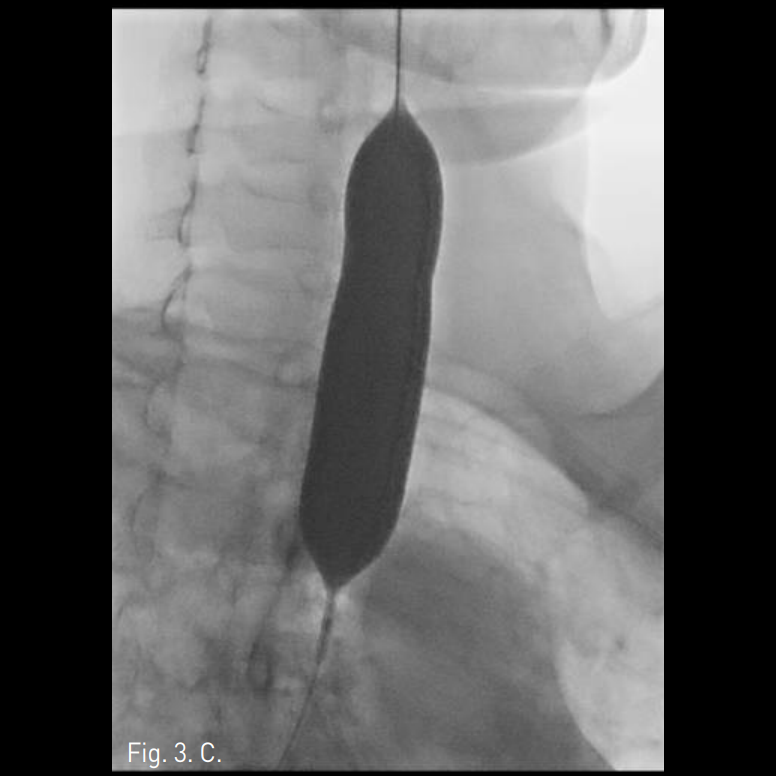

Fig. 2

Web-like circumferential stenosis is noted in the initial bronchoscopic evaluation.